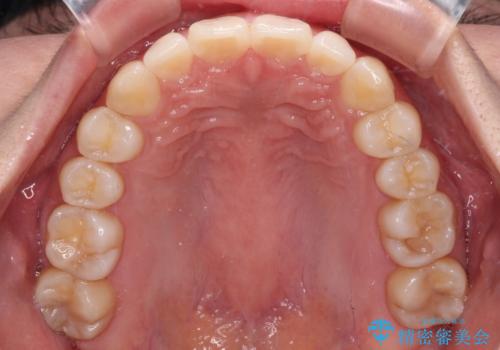

- 上顎前歯の隙間を気にして来院された患者様です。

下顎前歯が上顎前歯に食い込むような咬み合わせにより、上顎前歯が開いてしまっていたため、咬合高径の挙上により突き上げを改善するよう、インビザラインにより矯正治療を行うこととしました。

咬合高径の挙上により上顎前歯の突出感も改善することができ、整った口元となりました。